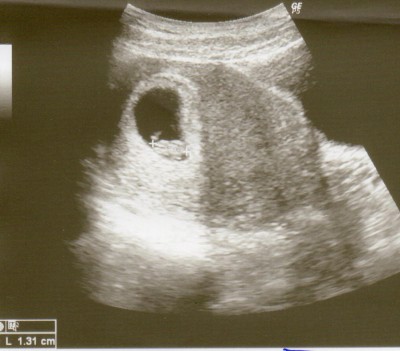

so jetzt versuche ich mal das Bildchen hochzuladen...